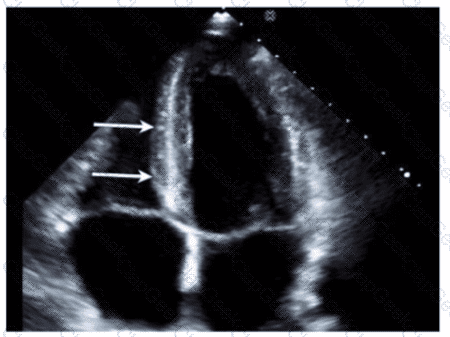

Which region of the aorta is being measured to assess the critical finding in this image?